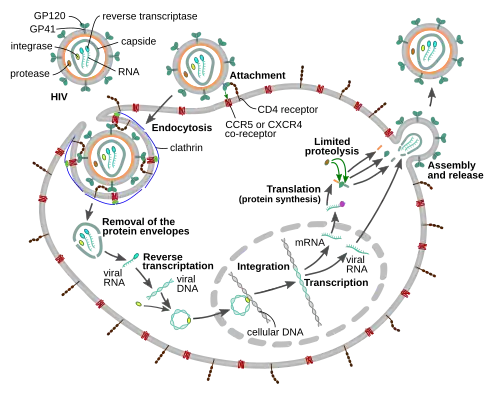

The HIV replication cycle

Entry to the cell

The HIV virion enters macrophages and CD4+ T cells by the adsorption of glycoproteins on its surface to receptors on the target cell followed by fusion of the viral envelope with the target cell membrane and the release of the HIV capsid into the cell.[59][60]

Entry to the cell begins through interaction of the trimeric envelope complex (gp160 spike) on the HIV viral envelope and both CD4 and a chemokine co-receptor (generally either CCR5 or CXCR4, but others are known to interact) on the target cell surface.[59][60] Gp120 binds to integrin α4β7 activating LFA-1, the central integrin involved in the establishment of virological synapses, which facilitate efficient cell-to-cell spreading of HIV-1.[61] The gp160 spike contains binding domains for both CD4 and chemokine receptors.[59][60]

The first step in fusion involves the high-affinity attachment of the CD4 binding domains of gp120 to CD4. Once gp120 is bound with the CD4 protein, the envelope complex undergoes a structural change, exposing the chemokine receptor binding domains of gp120 and allowing them to interact with the target chemokine receptor.[59][60] This allows for a more stable two-pronged attachment, which allows the N-terminal fusion peptide gp41 to penetrate the cell membrane.[59][60] Repeat sequences in gp41, HR1, and HR2 then interact, causing the collapse of the extracellular portion of gp41 into a hairpin shape. This loop structure brings the virus and cell membranes close together, allowing fusion of the membranes and subsequent entry of the viral capsid.[59][60]

After HIV has bound to the target cell, the HIV RNA and various enzymes, including reverse transcriptase, integrase, ribonuclease, and protease, are injected into the cell.[59] During the microtubule-based transport to the nucleus, the viral single-strand RNA genome is transcribed into double-strand DNA, which is then integrated into a host chromosome.

HIV can infect dendritic cells (DCs) by this CD4-CCR5 route, but another route using mannose-specific C-type lectin receptors such as DC-SIGN can also be used.[62] DCs are one of the first cells encountered by the virus during sexual transmission. They are currently thought to play an important role by transmitting HIV to T cells when the virus is captured in the mucosa by DCs.[62] The presence of FEZ-1, which occurs naturally in neurons, is believed to prevent the infection of cells by HIV.[63]

Clathrin-mediated endocytosis

HIV-1 entry, as well as entry of many other retroviruses, has long been believed to occur exclusively at the plasma membrane. More recently, however, productive infection by pH-independent, clathrin-mediated endocytosis of HIV-1 has also been reported and was recently suggested to constitute the only route of productive entry.[64][65][66][67][68]

Assembly and release

The final step of the viral cycle, assembly of new HIV-1 virions, begins at the plasma membrane of the host cell. The Env polyprotein (gp160) goes through the endoplasmic reticulum and is transported to the Golgi apparatus where it is cleaved by furin resulting in the two HIV envelope glycoproteins, gp41 and gp120.[88] These are transported to the plasma membrane of the host cell where gp41 anchors gp120 to the membrane of the infected cell. The Gag (p55) and Gag-Pol (p160) polyproteins also associate with the inner surface of the plasma membrane along with the HIV genomic RNA as the forming virion begins to bud from the host cell. The budded virion is still immature as the gag polyproteins still need to be cleaved into the actual matrix, capsid and nucleocapsid proteins. This cleavage is mediated by the packaged viral protease and can be inhibited by antiretroviral drugs of the protease inhibitor class. The various structural components then assemble to produce a mature HIV virion.[89] Only mature virions are then able to infect another cell.